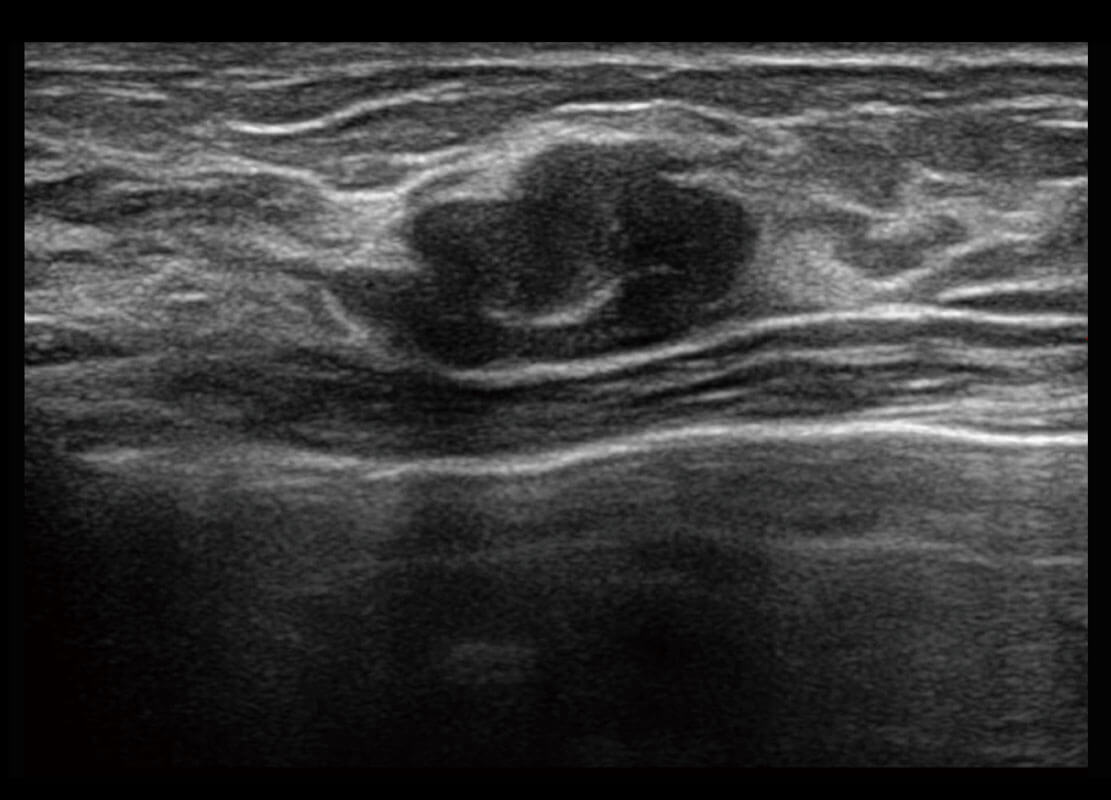

乳腺导管癌

乳腺癌显微血流